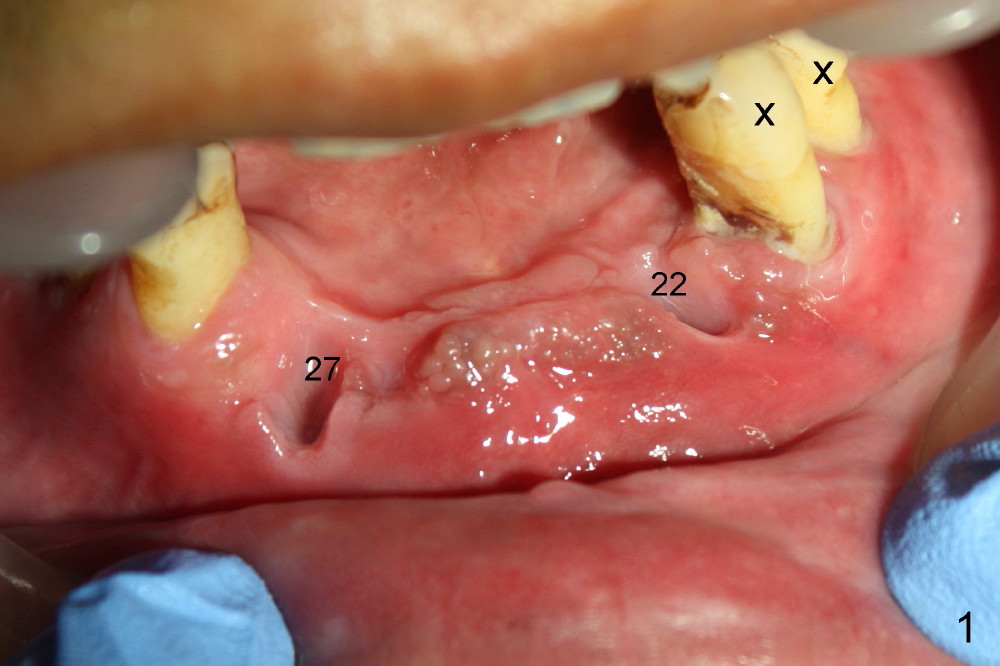

Osteotomy is initiated through the gingiva of the healing sockets at the sites of #22 and 27 (Fig.1) with difficulty (close surgery). The incisor crest incision is extended distal to the canine areas; an accessory oblique incision is supplemented to facilitate implantation (#22: 5x14 mm; #27: 4.5x17 mm) and expose the buccal defects (Fig.3,4, open surgery). The defects are grafted (Fig.5) and covered by collagen membrane (Fig.6). The incisions are closed and abutments are placed for immediate provisional (Fig.7).

Incision (open surgery) appears to help increase surgery safety and avoid complication (nerve injury) associated with immediate implant.